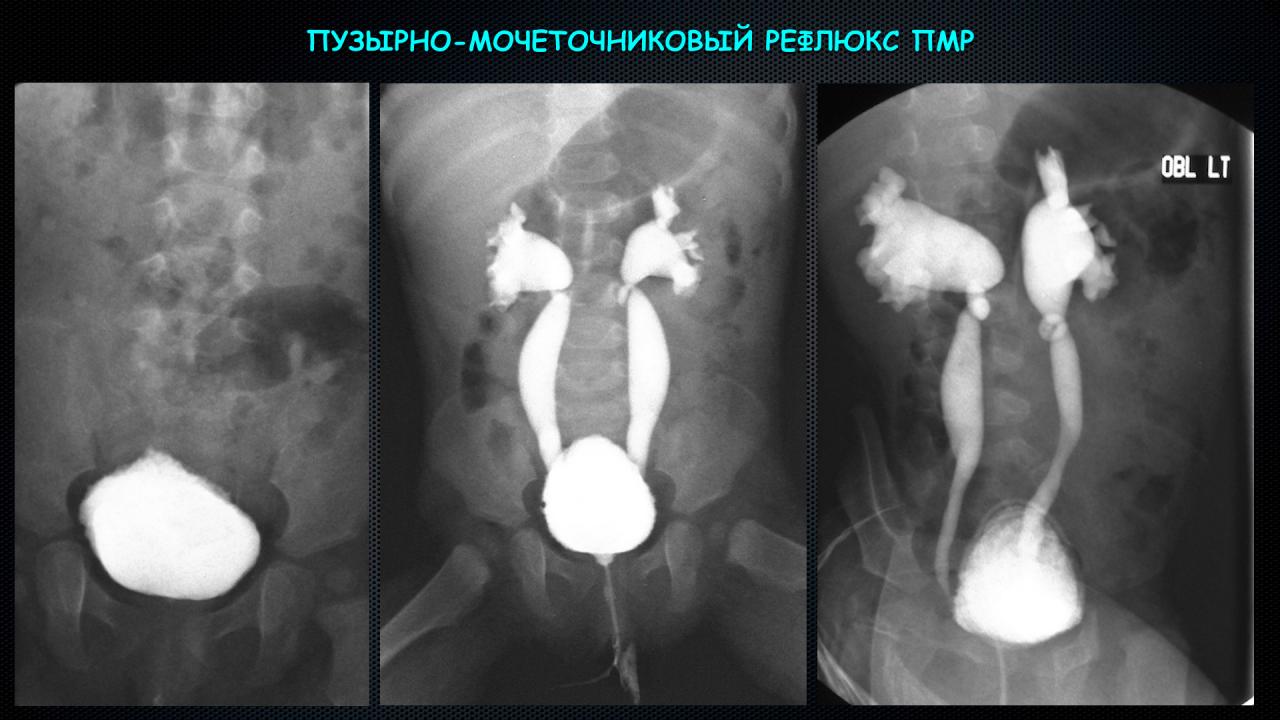

Рефлюксирующий мегауретер: Визуализация и медицинские изображения

Раздел: Фотопуть к знанию